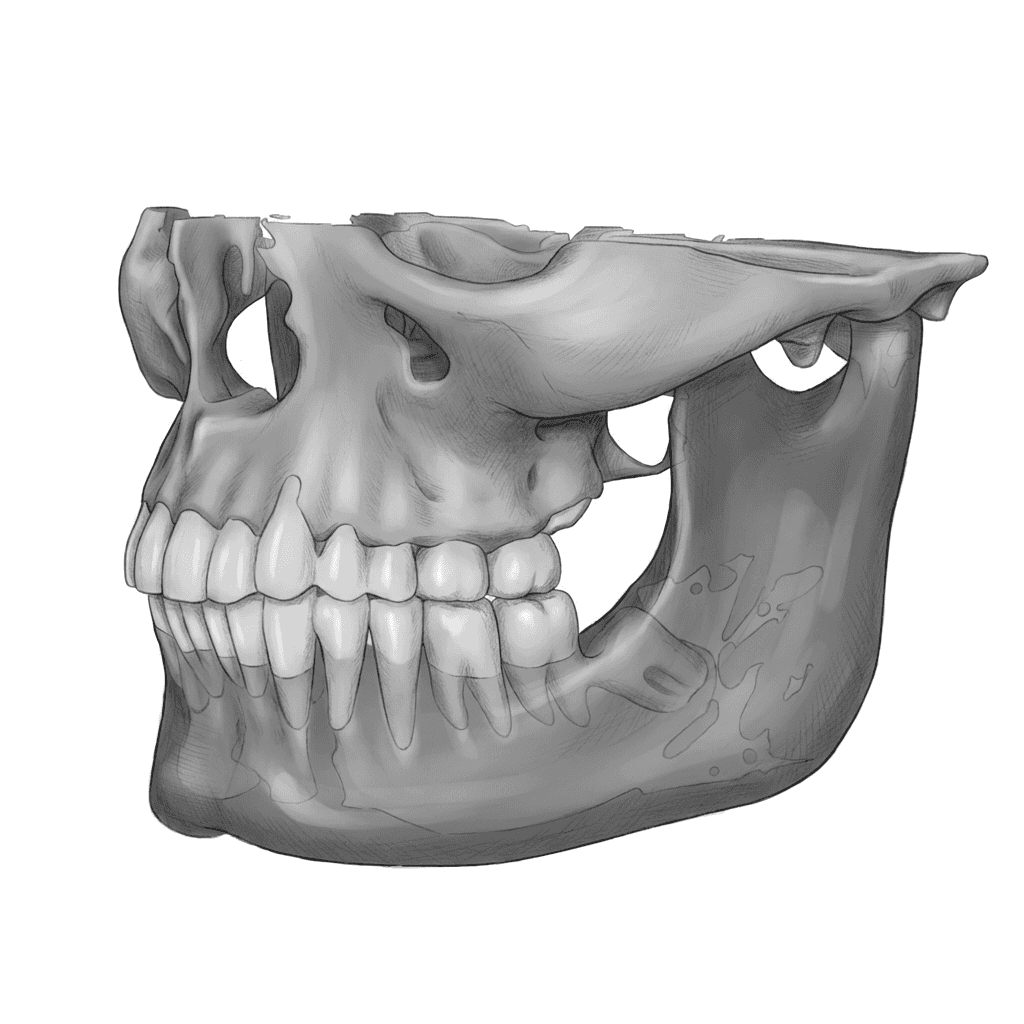

\\ Auto alignment

AI Aligns Scan and DICOM

CBCT and intraoral scans auto-align with AI's sub-millimeter precision. No tedious registration, no wasted time — just instant readiness.

AI auto-aligns CBCT and intraoral scans.

Planning begins immediately — zero prep time.

Zero manual registration or tweaking needed.

Detects anatomical landmarks and orientation automatically.